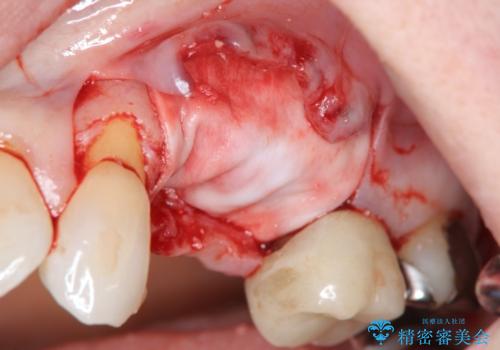

歯の穿孔(内部穴が開いている状態)破折等、歯を保存することができない問題が小臼歯には認められたので抜去を行います。

抜去後の補綴治療は長いブリッジではなくインプラント治療を希望されましたが、穿孔・破折による周囲の骨吸収をリカバリーすべく骨の造成を伴うインプラント治療を計画します。